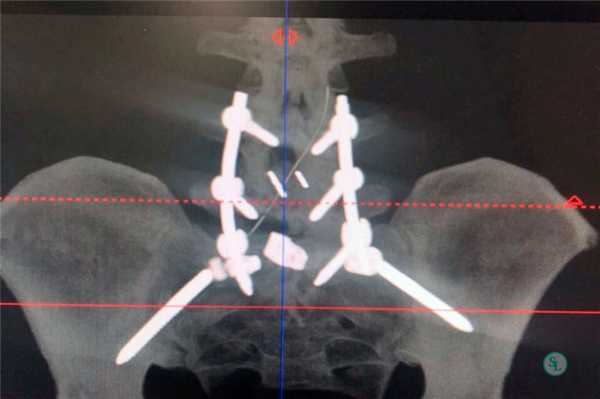

Чтобы иммобилизация позвоночно-двигательного сегмента была максимально надежной, нередко операция дополняется выполнением транспедикулярной фиксации. В таком случае устанавливаются специальные металлические конструкции, которые еще более упрочняют скрепление тел позвонков.

Для более прочной иммобилизации ПДС многие хирурги выполняют межтеловой спондилодез вместе с транспедикулярной фиксацией. Суть последней заключается в применении специальных конструкций, которыми дополнительно скрепляют тела позвонков.